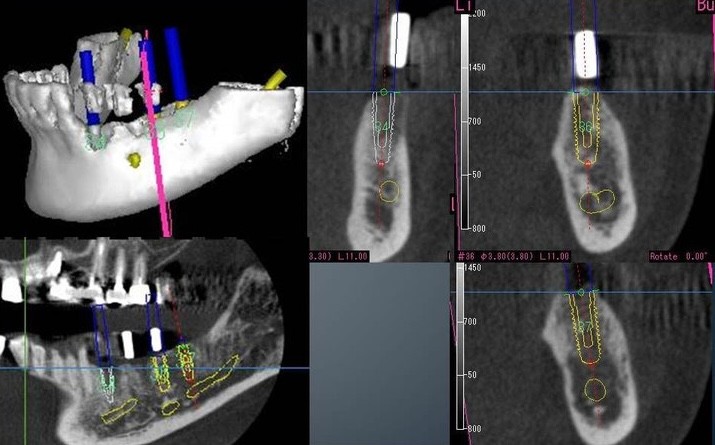

治療の際には、まず歯を失った原因をしっかり見極め、再び同じことが起こらないように配慮しています。術前にはCT撮影を行い、専用の画像解析ソフトを使って植立位置を慎重に決定。治療では2回法を用い、感染リスクを抑えながら確実な骨結合を目指しています。必要に応じて骨造成や歯肉の移植にも対応可能です。